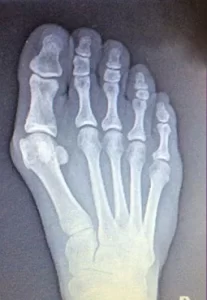

Operación de juanetes: antes y después

JUANETE LEVE

Juanete leve que afectaba a la estética del pie y generaba inseguridad. Se realizó una cirugía mínimamente invasiva que corrigieron la desviación sin dejar cicatrices visibles. Tras la intervención, la paciente ha mejorado notablemente la apariencia del pie y ha recuperado la confianza.